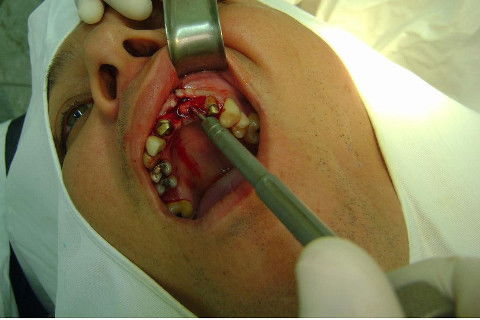

Cirurgia realizada hoje de manhã...No planejamento percebi medindo espessura do rebordo com especímetro que as medidas não estavam muito boas, ou o ideal, em torno de 4,5 a 5 mm ate´o terço médio do rebordo e melhorava no final, com 6 a 7 mm. Optei então por uma pequena expansão usando os expansores rosqueáveis. Aconteceu uma pequena fenestração na hora da fixação dos implantes, especialmente na região do 22 que fraturou o início da tábua óssea, mas não me preocupei porque não foi mais do que 2 mm de fratura em direção apical, o implante ficou infraósseo e com boa estabilidade (60 N no 21 e 40 N no 22). Esta fratura tb não deixou osso completamente solto, foi do tipo galho verde, deixei em posição e suturei normalmente. Só não fiz e nem estava planejado carga imediata mesmo, mais pelo motivo da oclusão inadequada do caso.

Fotos do caso